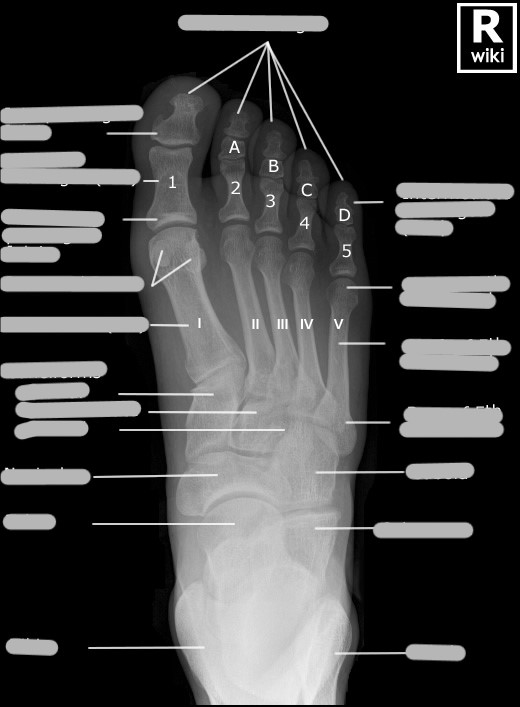

The top surface of the foot is anatomically ___, and is known as the ___ surface

The bottom surface of the foot is anatomically ___, and is known as the ___ surface

A PA projection of the foot could also be called a ___

An AP projection of the foot could also be called a ___

How many phalanges, metatarsals, and tarsals are in 1 foot?

metatarsals: 5

tarsals: 7

Does numbering of the foot digits start medially or laterally?

Is the head or base of the metatarsals distal?

The 1st metatarsal sometimes has sesamoid bones that are usually located ___